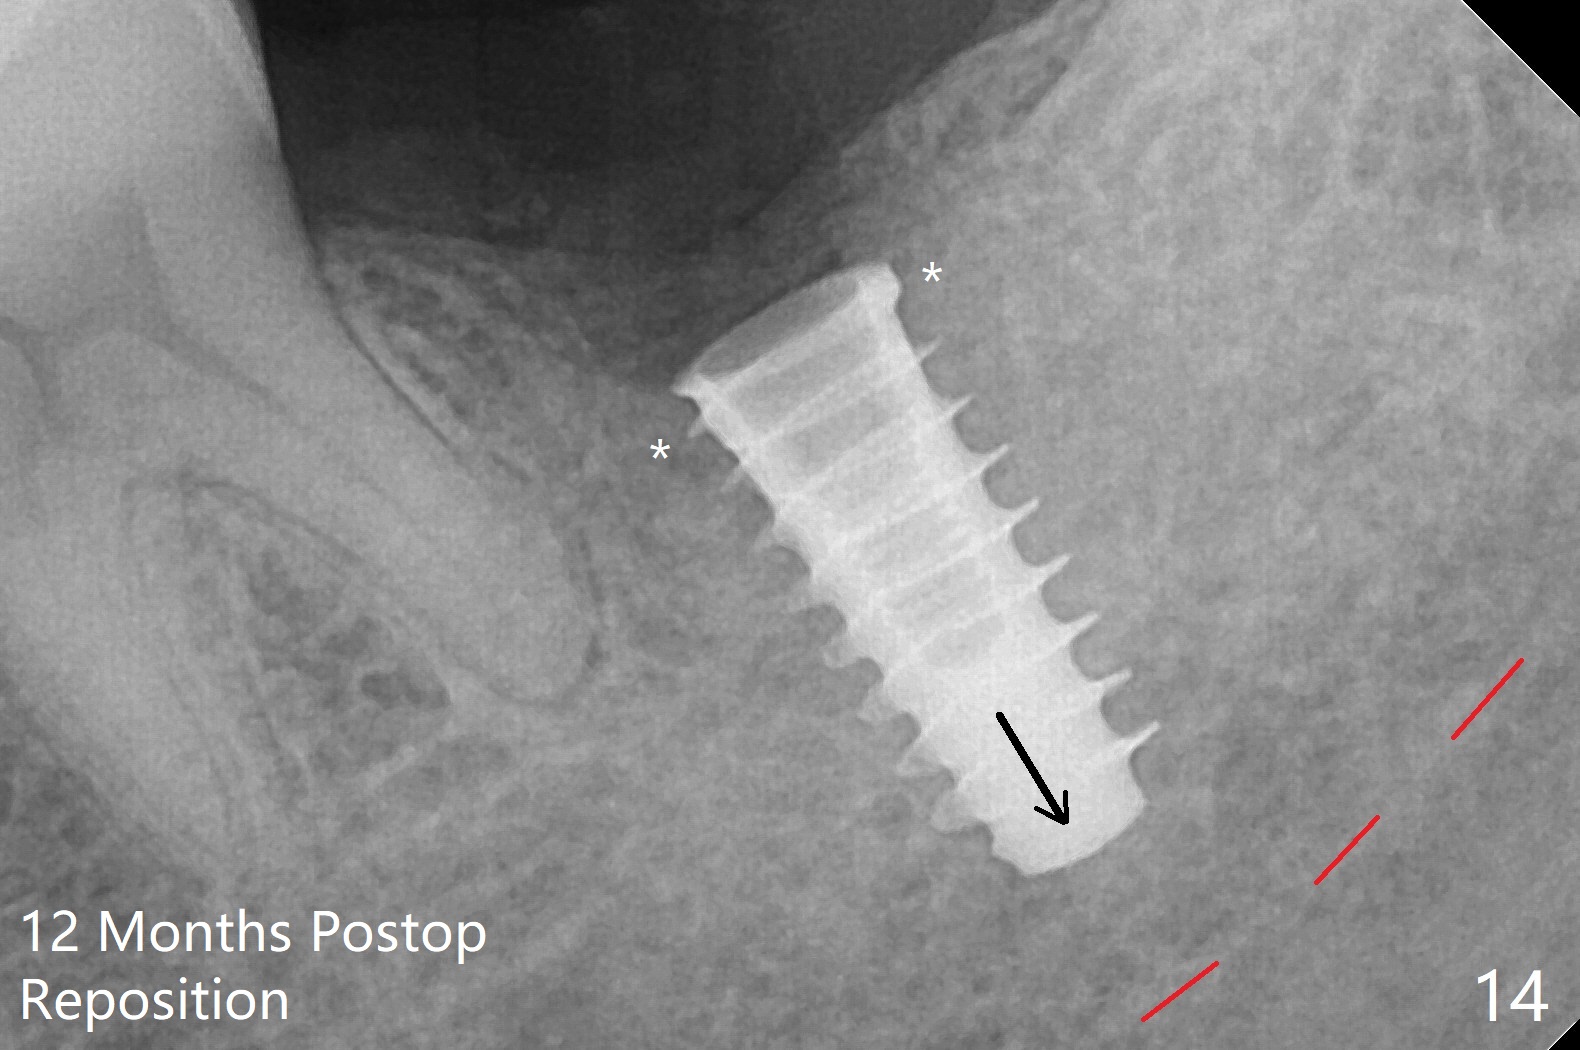

After placement of a 5x11 mm implant and cover screw at #18, allograft mixed with PRF (sticky bone) is placed in the peri-implant space, but it appears that bone density in the apical region (Fig.1 A) is lower than that in the coronal one (C) because of a constriction between the implant and the distal crest (*). Ideally the undercuts (Fig.2 *) of the extraction socket (black area) should be identified. Place bone graft in the undercuts (Fig.3 red circles) after osteotomy (white outlines) and before implant placement! A 4.5x1 mm temporary abutment is placed for an immediate provisional. The 2nd shortcoming of this case is that the implant is placed a little buccal. The papilla mesial to the immediate provisional (Fig.4 P) looks normal 4 days postop (no food impaction is expected when a final restoration is cemented). Additional acrylic (*) was placed to close a buccal gap when the provisional was seated with the temporary abutment. The patient reports loss of a piece of material in 4 days. It must be the additional acrylic, since it is absent 6 weeks postop (Fig.5). The provisional (Fig.5 P) looks wide, probably related to post-extraction gingiva and bone atrophy (Fig.6, 7 *). Bone graft (Fig.6 <) becomes a component of the gingival cuff. The provisional is re-trimmed for better oral hygiene. The gingival cuff is basically healthy 3.5 months postop, although the temporary abutment is loose and the implant is tender to rewinding and winding (Fig.8). The implant seems to remain non-osteointegrated 3.5 months postop (Fig.9). Although the bone density around the implant increases nearly 6 months postop (Fig.10), the implant remains tender when a 5x4(4) mm pair abutment is tightened. The healing abutment is reused. The bone density around the implant increases 11 months postop (Fig.11). Uncover is done with 5.5 mm profile drill. One month post uncover (12 months postop), the implant remains unstable (Fig.12). Prepare sticky bone x1. Make incision for exploration, including retightening the implant after Titanium brush and H2O2 Q-tip rubbing. If needed, a larger and shorter UF implant is a replacement (Fig.13). The implant is removed, cleaned with Titanium brushes and H2O2 in vitro and repositioned 12 months postop (Fig.14: arrow (gaps: post granulation tissue removal)). The gaps are regrafted with sticky bone and covered with PRF membrane and Cytoplast. Although the patient complains of severe pain the first 2-3 postop, the wound is apparently healing 12 days postop. The Cytoplast is exposed asymptomatic 5 weeks postop (Fig.16) and removed (Fig.17). The wound appears to have healed without loss of the bone graft (Fig.18).术后四个月伤口愈合,骨粉几乎没有丢失,有骨小梁形态(图十九:*)。切开,刮匙去骨,有一定硬度,即刻放置修复基台,完全就位(图二十),制备临时牙冠,牙周敷料固定组织瓣(没有缝线)。